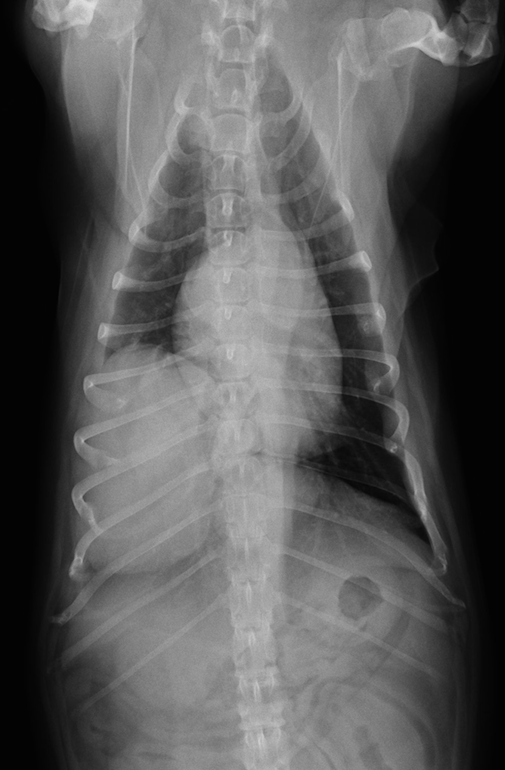

case.1

初診時

左側鼻腔のX線不透過像を認める。

化学療法4週後。